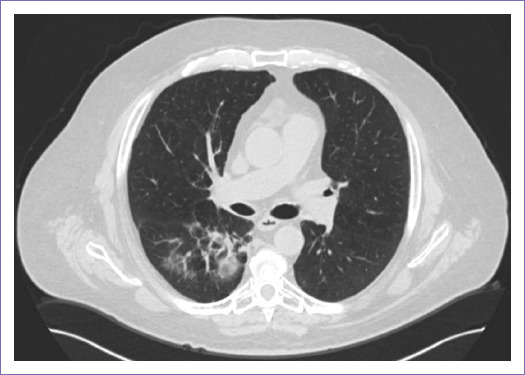

Cinco meses posteriores al inicio de gemcitabina se documenta por PET/CT y radiografía de tórax atelectasia del lóbulo superior derecho (Fig. 4), por lo que se decidió interconsulta a Neumología para posible colocación de stent bronquial y valorar inicio de radiocirugía.

Figura 4 Radiografía de tórax con hemitórax derecho con disminución en expansión secundario a opacidad parahiliar derecha con broncograma aéreo, condiciona retracción de la tráquea y mediastino.